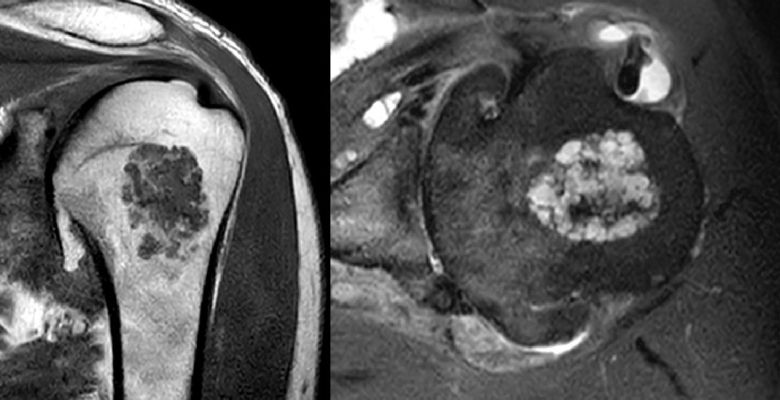

Revolutionising diagnosis and management of cartilage tumours

The musculoskeletal radiology department at BHP member the Royal Orthopaedic Hospital (ROH) has developed a new website designed to enhance the diagnosis and management of cartilage tumours.